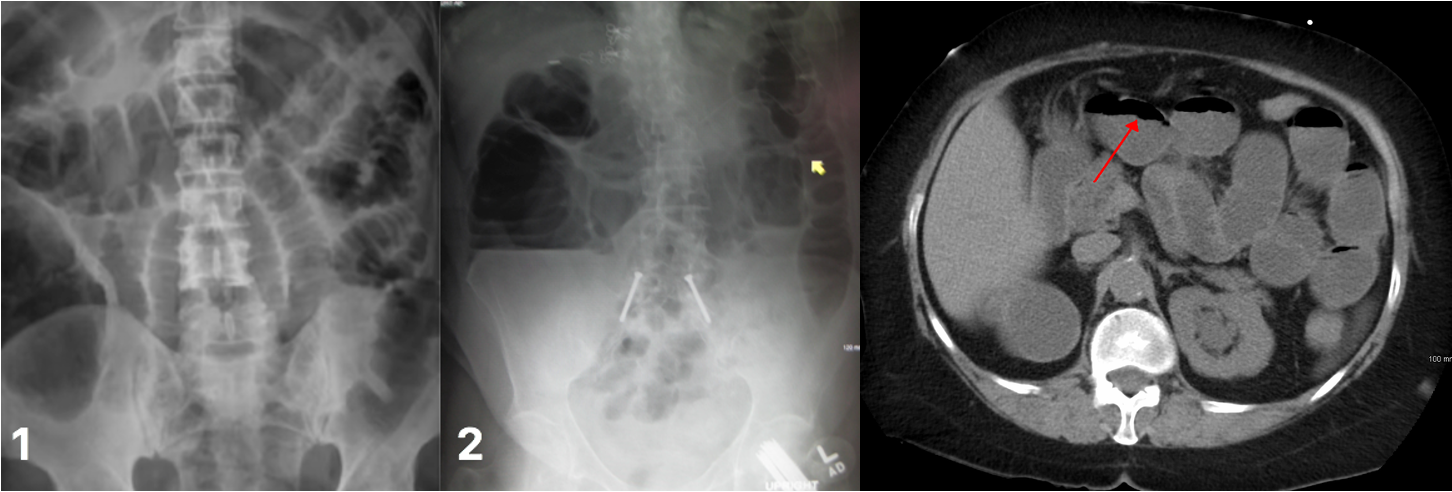

A) Mechanical bowel obstruction

is the interruption of normal passage through the bowel due to a structural barrier (Small or large)

Radiological appearances:

Dilatation of bowel loops proximal to the obstruction: 3-6-9 rule :To help guide the identification of bowel dilatation on imaging. Transverse diameter greater than the following indicates dilation: Small bowel > 3 cm Large bowel > 6 cm Cecum > 9 cm

- SBO: Dilated loops are predominantly central.

- LBOÂ : Dilated loops are predominantly peripheral.